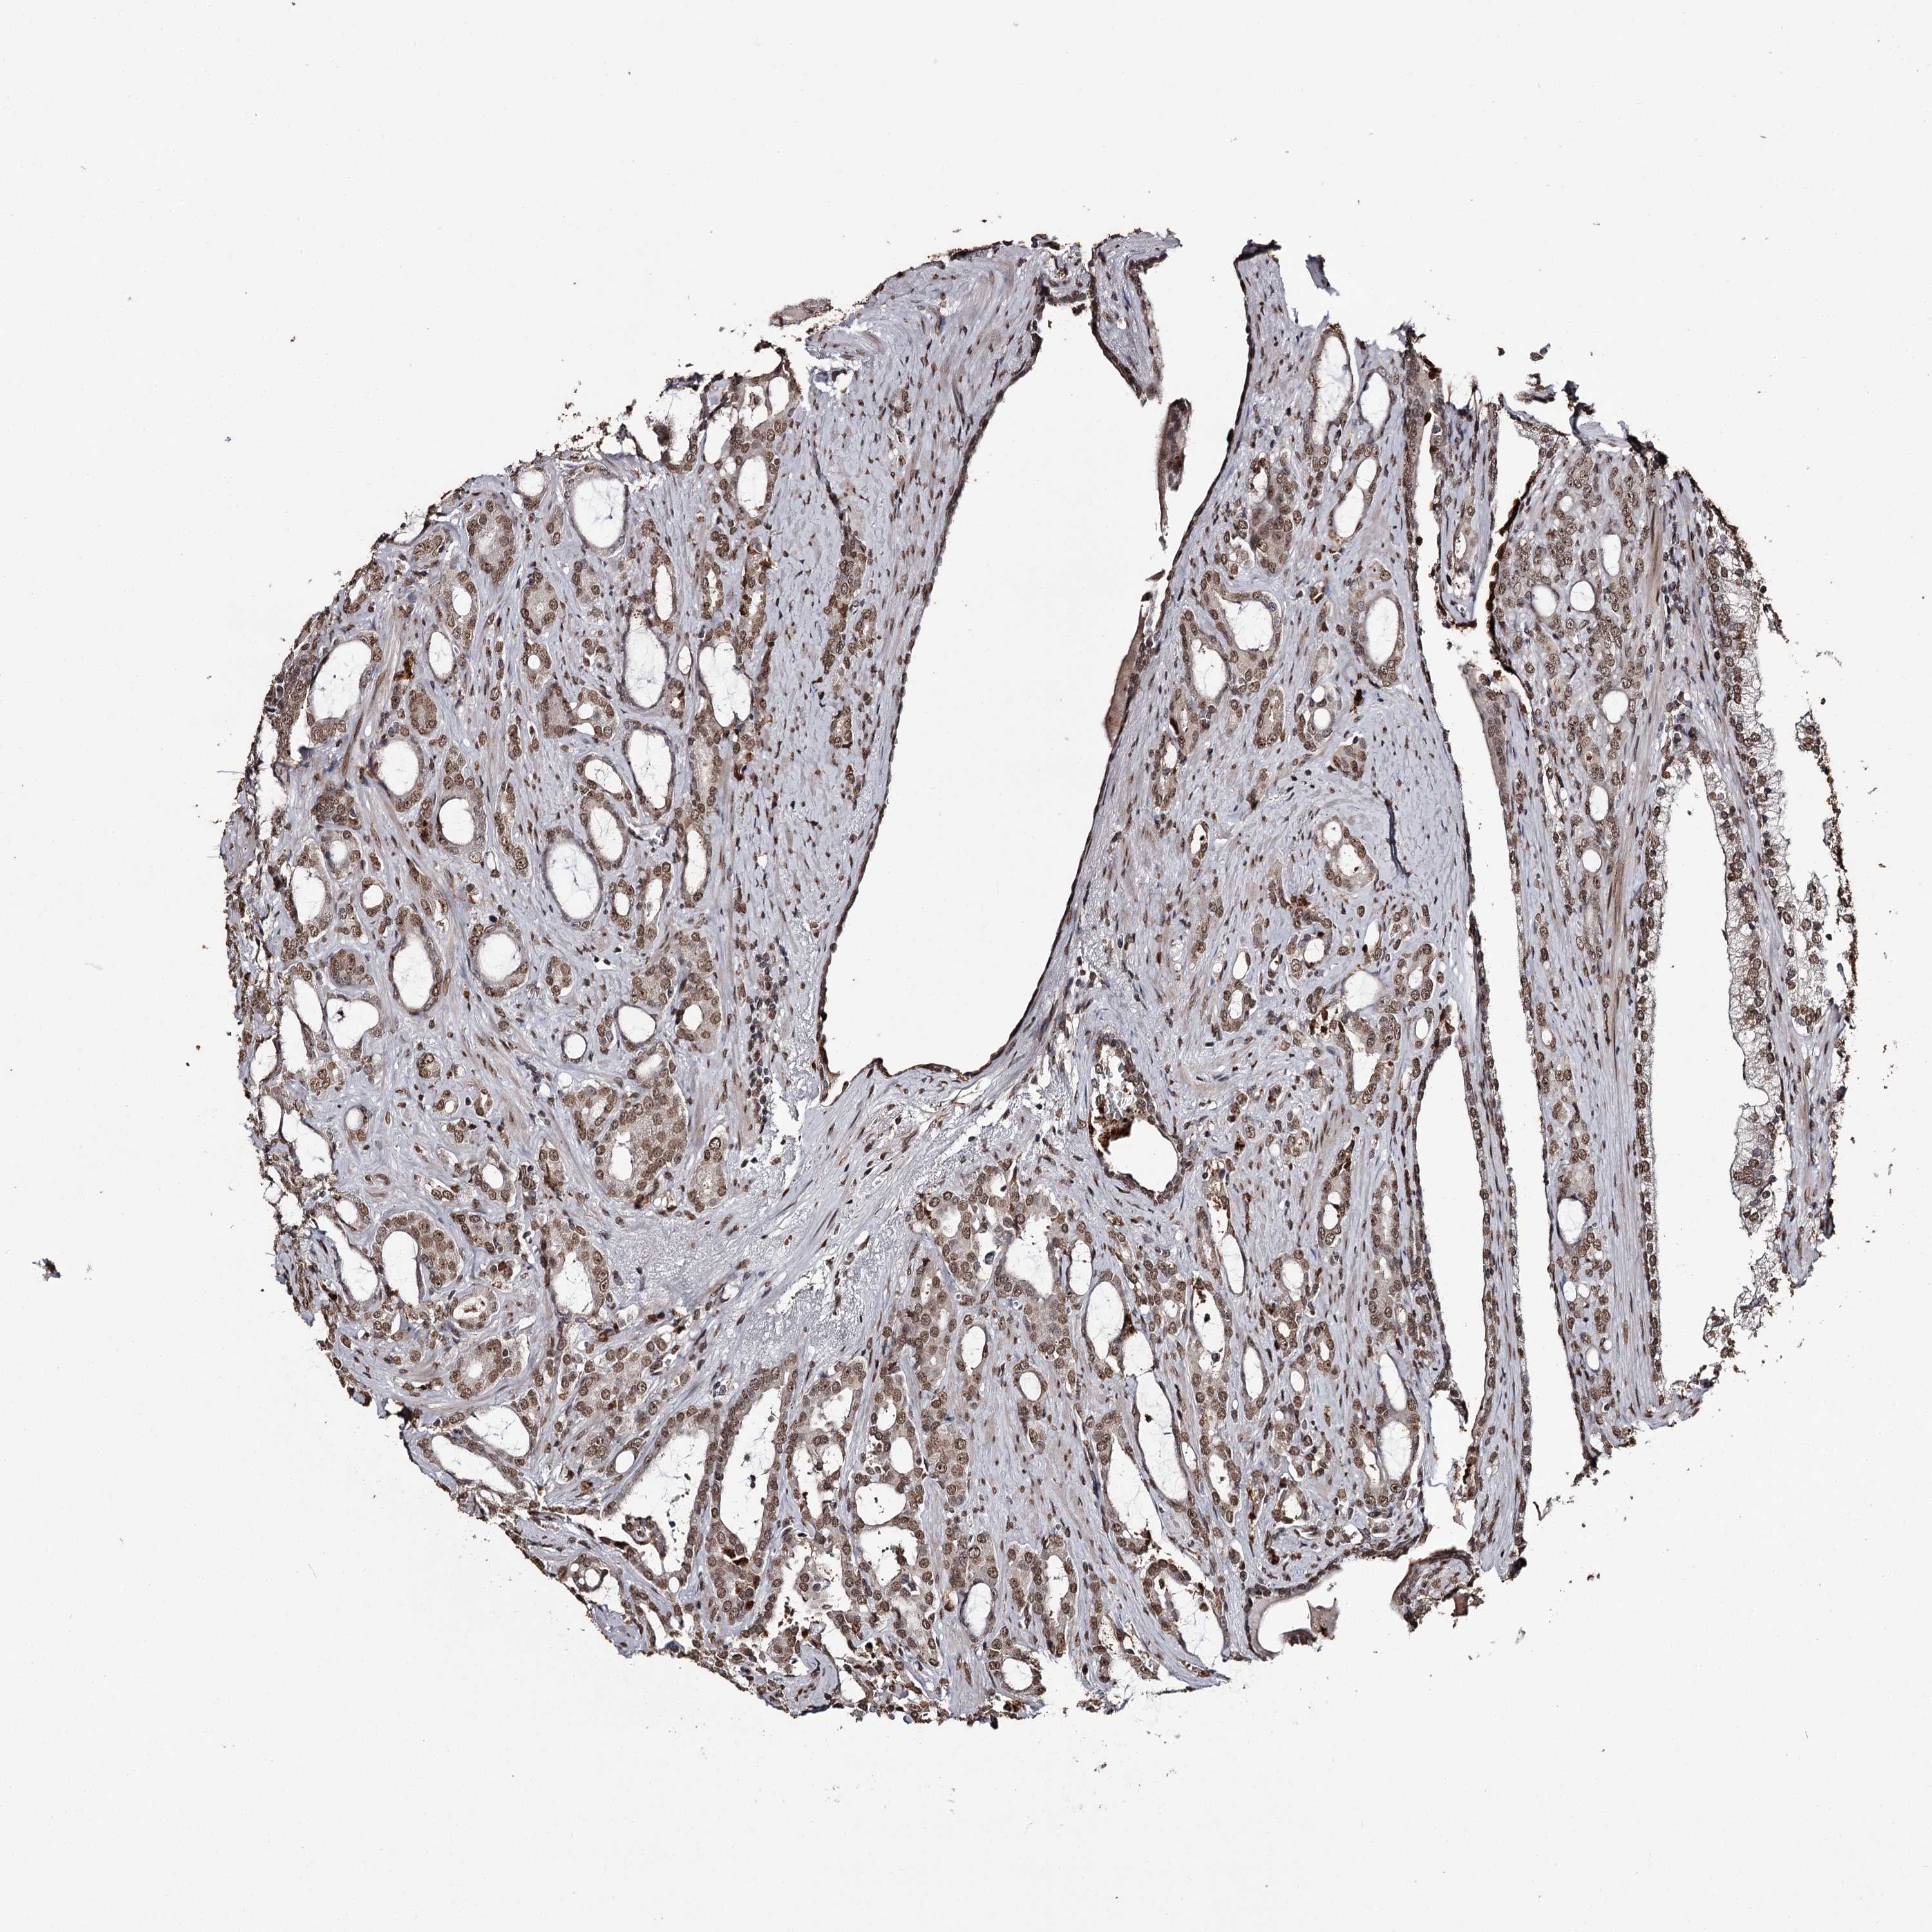

PROSTATE CANCER - Protein expressioni

A mouse-over function shows sample information and annotation data. Click on an image to view it in a full screen mode. Samples can be filtered based on level of antibody staining by selecting one or several of the following categories: high, medium, low and not detected. The assay and annotation is described here.

Antibody stainingi

Antibody staining in the annotated cell types in the current human tissue is reported as not detected, low, medium, or high, based on conventional immunohistochemistry profiling in selected tissues. This score is based on the combination of the staining intensity and fraction of stained cells.

Each image is clickable and will lead to virtual microscopy that enables deeper exploration of all samples and also displays staining intensity scores, fraction scores and subcellular localization as well as patient and tissue information for each sample.

Antibody HPA038732

Antibody HPA038733

Staining

High

Medium

Low

Not detected

Intensity

Strong

Moderate

Weak

Negative

Quantity

>75%

75%-25%

<25%

None

Location

Nuclear

Cytoplasmic/membranous

Cytoplasmic/membranous,nuclear

Adenocarcinoma, NOS

Adenocarcinoma, High grade

Adenocarcinoma, Low grade